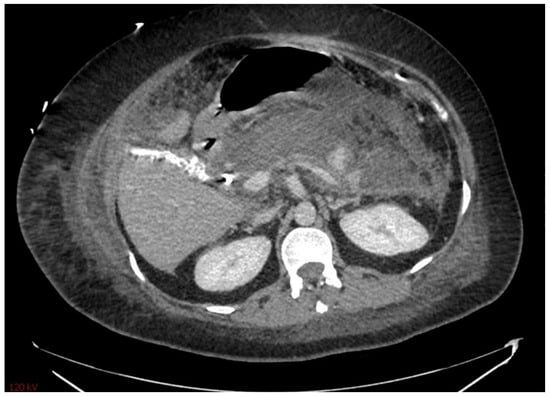

Multiple cytokines mediate a powerful pro-inflammatory immune response, such as tumor necrosis factor-alpha (TNF-a) and interleukins 1a, 1b, 6, and 18, exacerbating the initial pancreatic injury [37]. Pathologically, this appears as inflammation and can also be associated with a hemorrhage at the microscopic level (Figure 2 and Figure 3). The cytokine-mediated inflammatory cascade then extends the inflammatory cascade via lymphatic and systemic circulation into the liver, lungs, heart, kidneys, and gastrointestinal (GI) tract, leading to multi-organ injury [38]. This can cause systemic inflammatory response syndrome (SIRS), an early clinical feature that persists in cases of severe acute pancreatitis. Inflammation and damage to the GI tract can lead to bacterial translocation [39], and the species of bacteria involved are a predictive factor of disease severity, with Enterococcidae most frequently being associated with severe disease [40]. Obesity is also a predictive factor for moderate severity, and it leads to further deleterious effects through adipocyte lipolysis in the pancreas and adipose tissue [41,42] (Figure 2 and Figure 3).

Figure 3. Acute pancreatitis as seen at 10× magnification (H&E stain).